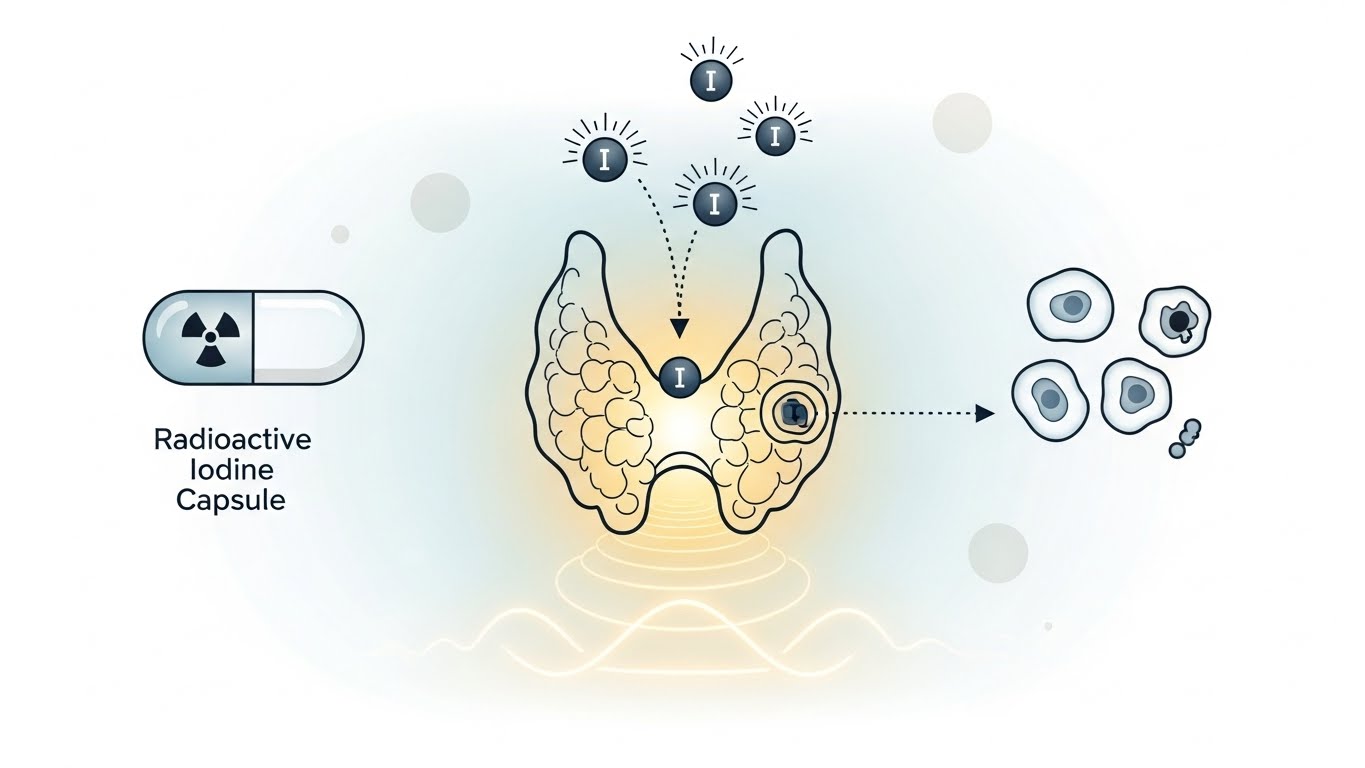

2. 방사성 요오드 치료

- 방사성 요오드를 복용해 갑상선 조직을 선택적으로 파괴

- 효과가 강력하며 장기적으로 효과 유지